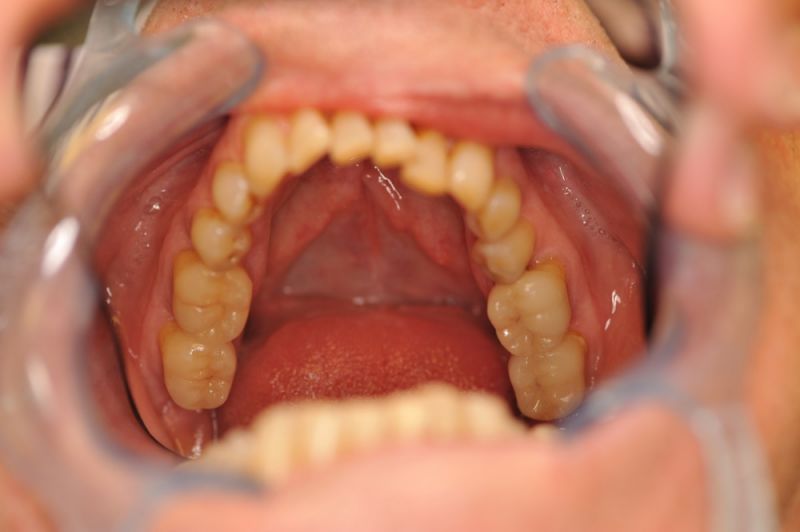

73 jähriger CMD-Patient im Recall

Seit 5 Jahren ist der Zustand des Patienten vollkommen unverändert!

Die aktuellen Taschentiefen liegen bei 2 Millimeter! Auch im Bereich der Implantate!

Auch in diesem Fall zeigt sich, dass es gerade bei älteren Patienten sinnvoll ist umfangreiche, festsitzende Versorgungen umzusetzen, so lange sich der Patient noch in einer gesundheitlich guten Konstitution befindet, um dann für die kommenden Lebensjahre Substanz vorzufinden, mit der man "arbeiten" kann.